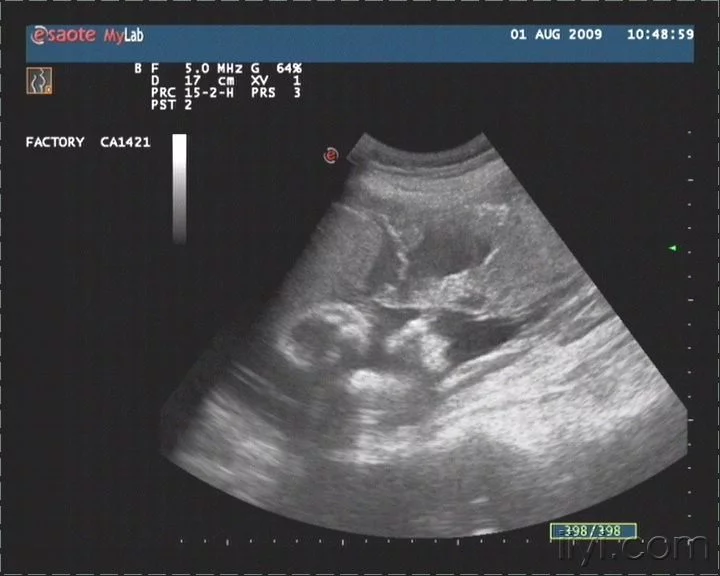

胎盘血池

胎盘血池(也称胎盘静脉池)在胎盘绒毛中心部分无绒毛处,胎盘实质中的较大的近圆形暗区,可见细密光点从侧壁流入暗区内,若范围大,将影响绒毛血流的交换。